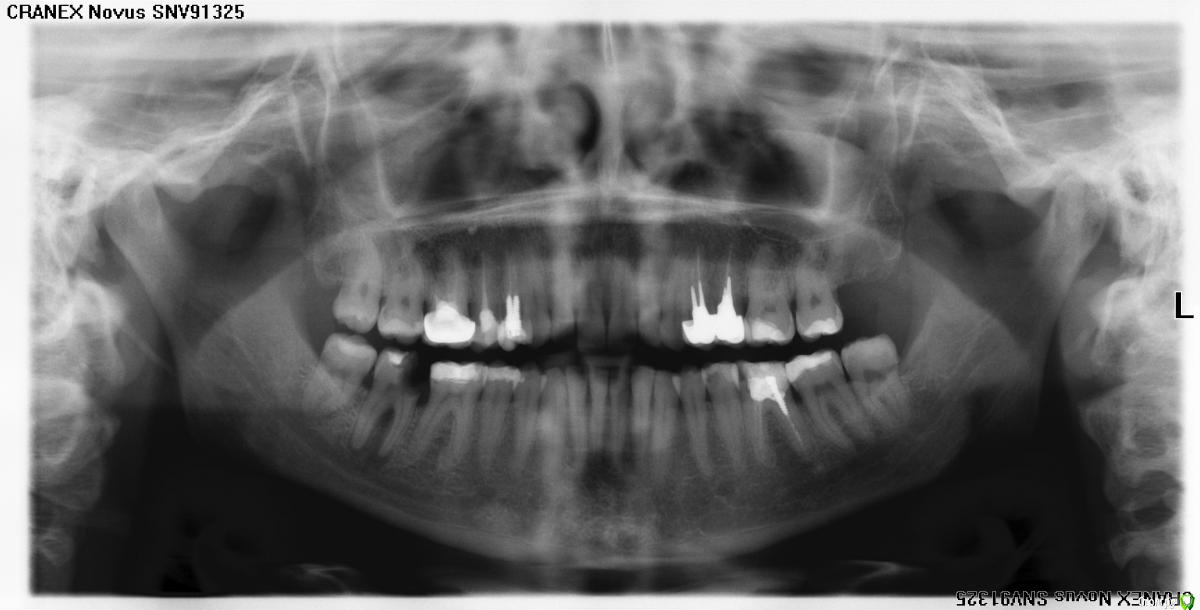

KCatherine Опубликовано 23 марта, 2015 Поделиться Опубликовано 23 марта, 2015 (изменено) Добрый день, два врача , приговорили зуб к удалению, но хотелось бы все таки убедиться, что это единственный выход. Нижняя семерка справа. И есть ли смысл вообще за него бороться , либо сразу настроиться на имплантацию ? Изменено 23 марта, 2015 пользователем KCatherine Ссылка на комментарий

KCatherine Опубликовано 23 марта, 2015 Автор Поделиться Опубликовано 23 марта, 2015 (изменено) Вам озвучили причину удаления?Гранулемы на корне зуба и из-за этого отмирание костной ткани. Сейчас десна возле зуба остается немного припухшая. Изменено 23 марта, 2015 пользователем KCatherine Ссылка на комментарий

KCatherine Опубликовано 23 марта, 2015 Автор Поделиться Опубликовано 23 марта, 2015 (изменено) Зуб был с нервом , но очень сильно нарощенный, какое-то время назад начал болеть при надавливании, но я почему-то списала на зуб мудрости, т.к. боль не была четко локализованна. Буквально неделю назад скололась часть и опухла десна, сейчас припухлость десны почти спала и сам зуб не болит, но по снимку врачи не обнадеживают. Изменено 23 марта, 2015 пользователем KCatherine Ссылка на комментарий

Гарриевич Опубликовано 23 марта, 2015 Поделиться Опубликовано 23 марта, 2015 если дело только в гранулеме, то лечится без проблемно сам зуб сильно разрушенпоэтому сначала нужно убрать весь кариес и разрушенные ткани и окончательно решать после этого 2 Ссылка на комментарий